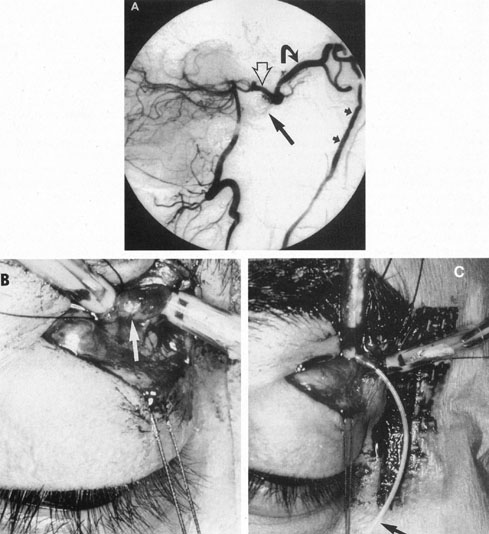

The therapy for AVMs has been reviewed elsewhere.91–93 The preferred treatment remains complete surgical excision of the malformation. However, significant advances in endovascular and radiosurgical techniques have resulted in a marked increase in the use of multimodal, staged approaches to AVM treatment. A variety of intravascular techniques use embolization91 with materials such as particles of polyvinyl alcohol (PVA), platinum coils, and injection of liquid N-butyl-cyanoacrylate (NBCA) adhesive (Fig. 11). Complications of intravascular embolotherapy include vessel perforation by the catheter, migration of embolic materials, and infarction and hemorrhage of normal brain.

Fig. 11. Embolization of middle cerebral vessels that supply occipital lobe arteriovenous malformation (AVM). The patient had a subarachnoid and intraparenchymal hemorrhage that produced a left homonymous field defect. A: Right carotid arteriogram demonstrates contribution via posterior communicating artery to a right occipital lobe AVM. B: Vertebral injection. The arrow points to the enlarged right posterior cerebral artery that is a major feeder of the AVM. C: Right carotid arteriogram during glue embolization procedure. The arrow points to a catheter as it traverses the segment seen in (B). The catheter was advanced via the internal carotid artery but is positioned far posteriorly. D: Upper branches to the AVM now are occluded, with residual low-flow vascularization via the middle cerebral artery. E: Skull film showing radiopaque glue within the AVM and blood vessels previously supplying it. The patient had a persistent visual field defect but greatly reduced headache and no persistence of subjective bruit. (Courtesy of Dr. Joseph Horton.)

Mechanisms of delivery of radiation therapy to AVMs include those of the linear accelerator (LINAC), gamma knife, and heavy charged particle beam (proton and helium ion Bragg-peak radiosurgery). Stereotactic radiosurgery is most commonly administered by gamma knife for a variety of intracranial disorders to include tumors and vascular malformations.94 Pollock et al61 believe that stereotactic radiosurgery is 80% effective for AVMs less than 3 cm in average diameter, within a latency period of 2 to 3 years, but the patient is at risk during the interval until obliteration of the lesion.